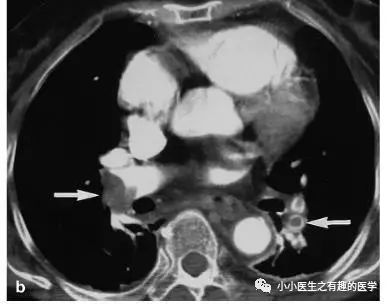

增强CT对比,一目了然。

上面的患者,增强CT放大了。

下面是另外一个